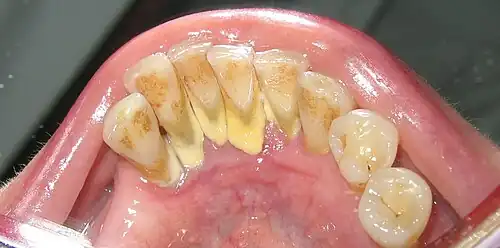

Microbial profiles differ significantly between dental plaque and dental calculus although calculus forms from plaque.[8] The protein and metabolic profiles also have distinct taxonomic and metabolic functions between dental plaque and dental calculus.[8] As the oral biofilm develops, taxonomic shifts take place due to the structural and resource changes in the biofilm through time.[8] The early colonizers are typically facultative anaerobes that are saccharolytic, however, as the biofilm grows and oxygen is depleted, methanogens and sulfate-reducers increase in abundance and the early colonizers decrease.[8] This matured biofilm community is the one preserved in dental calculus.[8] Ancient dental calculus often contain high amounts of proteolytic obligate anaerobes that resemble the mature biofilm including Tannerella, Porphyromonas, Methanobrevibacter, and Desulfobulbus. [8][3] Historic calculus samples have less metabolite profile diversity (amino acids, carbohydrates, cofactors, vitamins, energy, lipids, nucleic acids, peptides) suggesting that individual phenotypes may be lost through metabolite degradation over time.[6] One problem with sampling ancient dental calculus is that little is known about age-related protein degradation.[6] Lipids are some of the best preserved metabolites and are stable over time giving them a promising focus for further evolutionary studies of dental calculus.[6] Phenylalanine, succinate, hydrocinnimate, cadaverine, and putrescine are all metabolite markers of periodontal disease that can be found in calculus.[6] Bacterial composition of ancient dental calculus is similar to modern but with the exception of higher amounts of Bacillota and Actinomycetota.[9] Human oral bacteria underwent a distinct shift to a disease-associated configuration with the transition from hunter-gatherer to farming in early Neolithic and then stayed relatively consistent through the Medieval period (~400 years BP).[9] In contrast the modern oral environment is less diverse and has high levels of cariogenic bacteria like S. mutans.[9]

Human microbiota plays a central role in health and diseases and disruption of the microbiome leads to dysbiosis (the relationship between microbiota and host is linked to illnesses etc.).[10] Unlike other human microbiomes, the oral microbiome is in dysbiosis causing disease in a majority of people in their lifetime.[3] The human oral microbiome has long served as a holding tank for a wide variety of opportunistic pathogens involved in both local and systemic disease.[3] The oral microbiome also harbors a diverse variety of presumed antibiotic resistant genes.[3] An abundance of immune system proteins both inflammatory (myeloperoxidase, azurocidin, lysozyme, calprotectin, elastase) and anti-inflammatory (α-1-antitrypsin and α-1-antichymotrypsin) are found in ancient dental calculus.[3] This conservation of immune system proteins is strongly supportive of their role in periodontal inflammation and disease.[3] Dental caries (tooth decay) and periodontal disease were both rare in pre-Neolithic hunter-gatherer societies.[9] Both increased following the transition to an agricultural diet, insinuating there was a major impact on the human oral microbiome.[9] The farming populations contained more periodontal disease-associated taxa such as P. gingivalis, Tannerella and Treponema.[9] Tannerella forsythia being the most prevalent human oral pathogen found in ancient dental calculus up to date.[2]